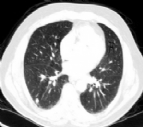

ESTUDO HOLANDÊS NÃO MOSTROU BENEFÍCIO NO RASTREAMENTO ANUAL POR TOMOGRAFIA PARA CÃNCER DE PULMÃO.

Os resultados dos 5 anos do estudo holandês Screening Trial Lung Cancer (DLCST) não mostraram benefício da mortalidade no rastreio anual para câncer de pulmão com tomografia computadorizada de tórax (TC). Houve a identificação de mais cânce...